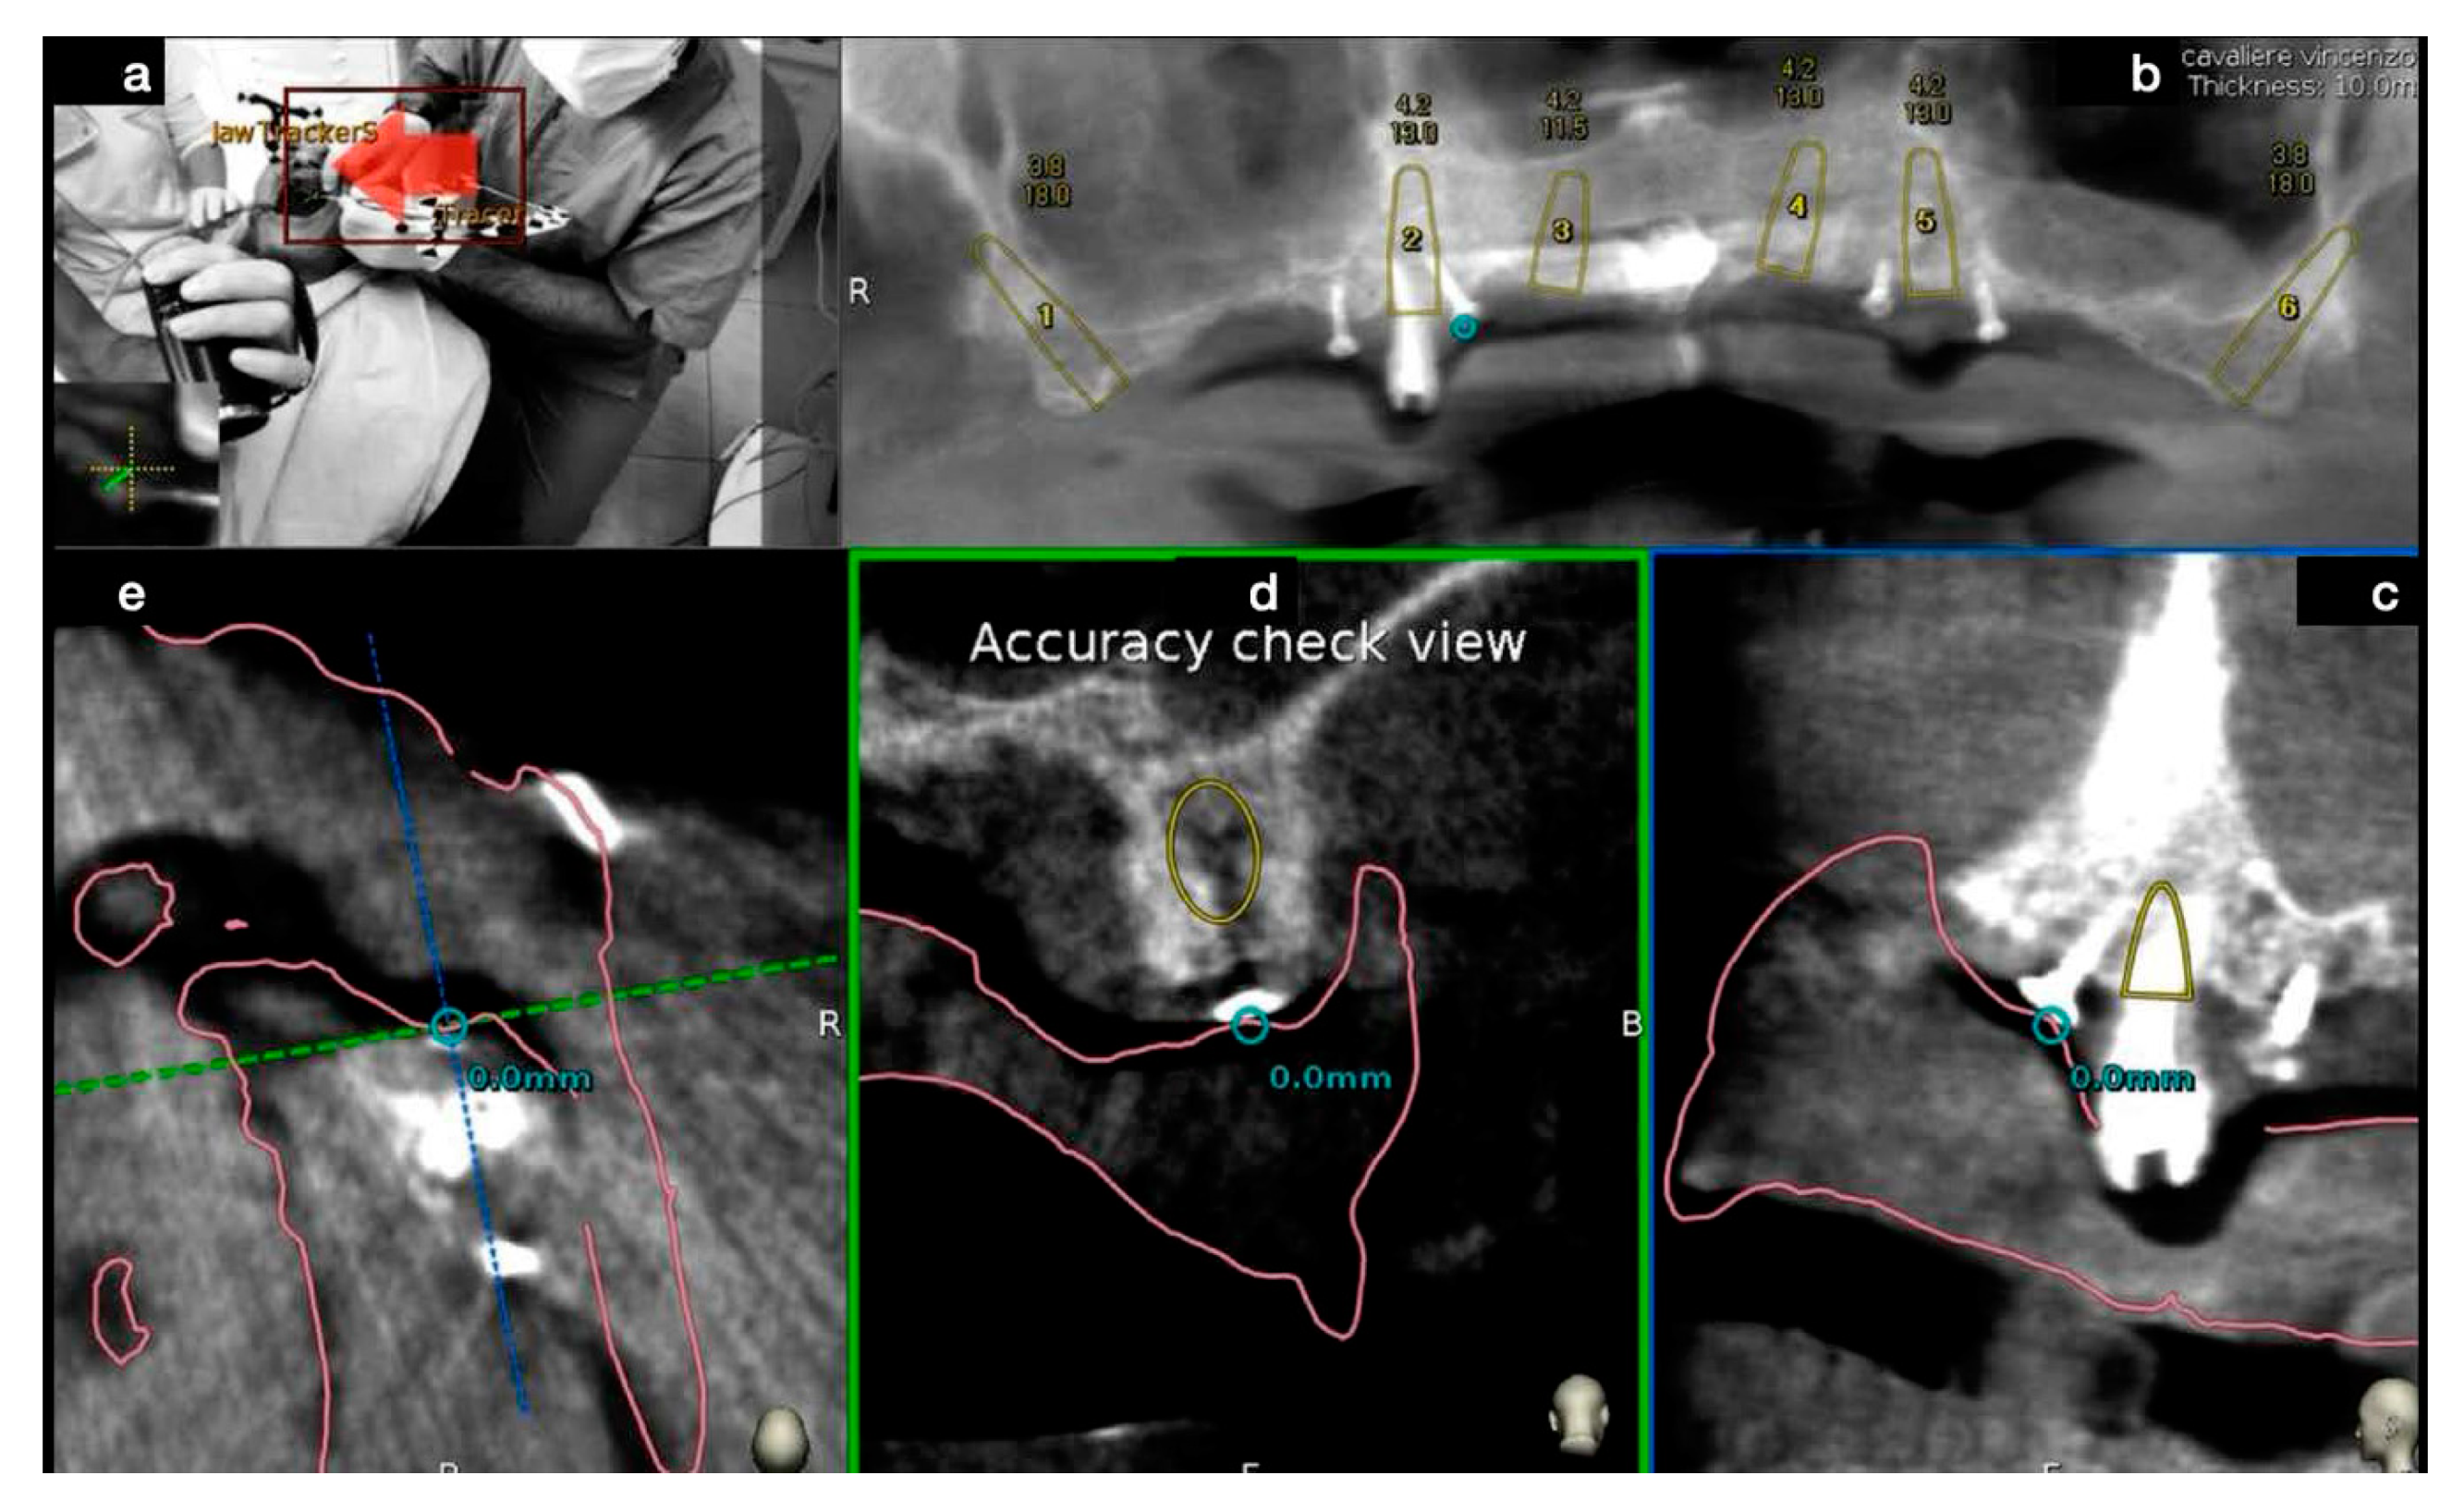

3.2. DCAI Approach Clinical Case